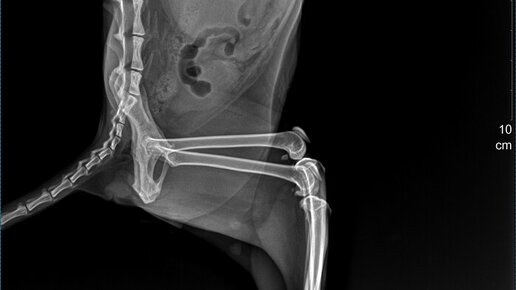

Сегодня моего кота приезжал посмотреть знакомый ветврач и с казал что его надо срочно везти в ветклинику и делать ему рентген в боковой проекции и анализы крови. Сказал что у него правая почка увеличена в размерах раз в пять. Предположительный диагноз: Гидронефроз почки? Отвез на рентген. Вот два снимка которые сегодня ему сделали. Рентгенолог говорит что на снимках она ничего не видит, кроме того что правая почка сильно увеличена в размере и ему надо делать еще и узи! В этой клинике где я был сегодня узи нет...